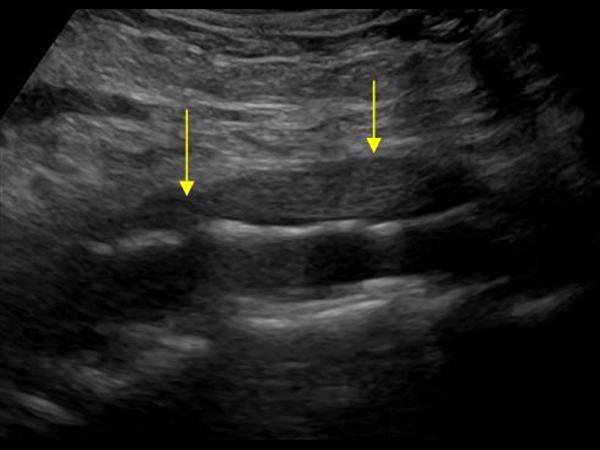

УЗИ лимфоузлов при лимфоме Ходжкина